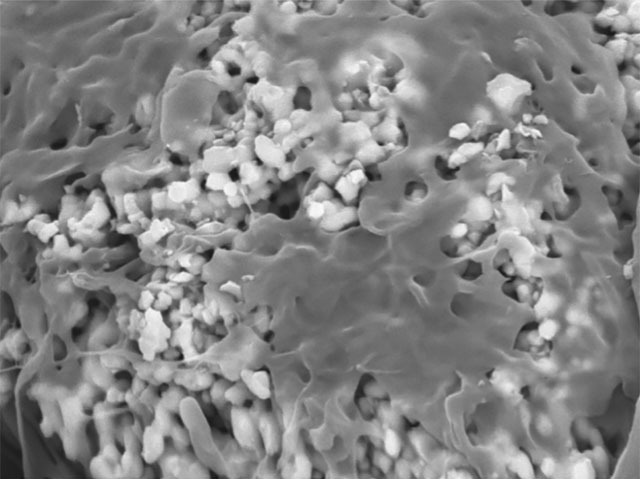

Today, replacing damaged bones with ones grown in a lab is already a reality. Scientists can grow mesenchymal stem cells (MSCs) from the patient’s bone marrow on a porous ceramic scaffold, as shown in this scanning electron microscope image, and attach it to their healthy bone. However, MSCs can also turn into muscle or fat cells, so it’s vital to ensure that they turn, or differentiate, into bone cells. The ceramic scaffold plays an important role in this: like the supporting scaffold of real bone, it contains calcium which induces MSCs to differentiate into bone cells rather than muscle or fat. Researchers are studying how calcium does this, by finding out which genes were activated at various times after the MSCs were placed on the scaffold. This will help test new scaffolds, with different shapes or components, for how effective they are at helping the cells differentiate.